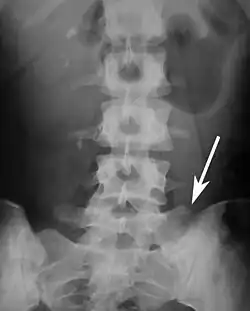

Lumbarization is an anomaly in the spine. It is defined by the nonfusion of the first and second segments of the sacrum. The lumbar spine subsequently appears to have six vertebrae or segments, not five. This sixth lumbar vertebra is known as a transitional vertebra. Conversely the sacrum appears to have only four segments instead of its designated five segments. Lumbosacral transitional vertebrae consist of the process of the last lumbar vertebra fusing with the first sacral segment. [1] While only around 10 percent of adults have a spinal abnormality due to genetics, a sixth lumbar vertebra is one of the more common abnormalities. [2]

Sacralization of the fifth lumbar vertebra (or sacralization) is a congenital anomaly, in which the transverse process of the last lumbar vertebra (L5) fuses to the sacrum on one side or both, or to ilium, or both. These anomalies are observed in about 3.5 percent of people, and it is usually bilateral but can be unilateral or incomplete (ipsilateral or contralateral rudimentary facets) as well. Although sacralization may be a cause of low back pain, it is asymptomatic in many cases (especially bilateral type). Low back pain in these cases most likely occurs due to biomechanics. In sacralization, the L5-S1 intervertebral disc may be thin and narrow. This abnormality is found by X-ray.